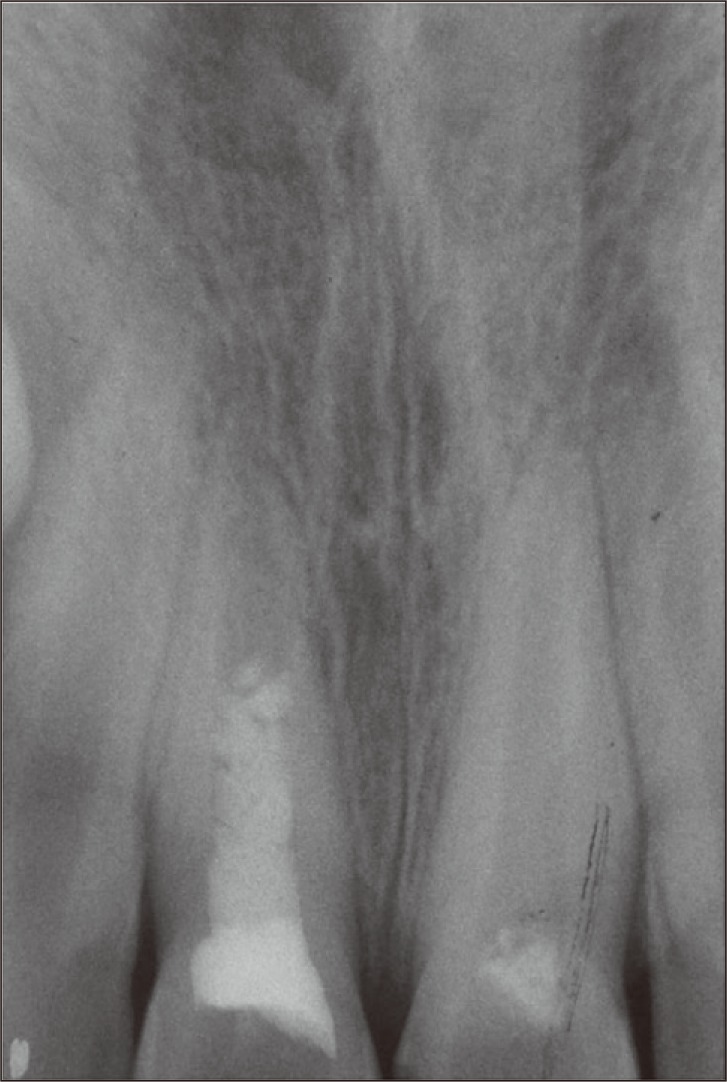

A 9-year-old boy was referred to the Department of Endodontics with pain on chewing and localized swelling on the anterior region of maxilla and a history of prior impact trauma three months previously. His medical history was non-contributory. Clinical examination showed complicated crown fracture on both maxillary central incisors. A large pulpal exposure, sensitivity to palpation and percussion and also localized swelling on the buccal mucosa of the right central incisor was observed. Cold thermal test elicited no response in this tooth. Left central incisor with a pinpoint pulpal exposure had no sensitivity in periapical tests and showed lingering painful response to cold test. Radiographic examination revealed that the fractured teeth had immature apices, and a radiolucent periapical lesion was observed adjacent to the right central incisor (Figure 1a). Based on clinical and radiographic examinations, the definitive diagnosis was irreversible pulpitis in the left central incisor and pulpal necrosis with symptomatic apical abscess in the right central incisor. Considering the immaturity of the teeth, the first treatment option was vital pulp therapy for the left central incisor and revascularization of the right one.

Under local anesthesia with 2% Lidocaine and 1 : 800,000 epinephrine (Xylocaine 2%, Dentsply, Addlestone, UK) and rubber dam isolation, an access cavity was prepared for the left central incisor. Coronal pulp tissues were removed by using a high-speed sterile long shank round diamond bur under copious water spray. The area was rinsed with normal saline solution and hemostasis was achieved by a cotton pellet moistened with 5% sodium hypochlorite (NaOCl). White Mineral Trioxide Aggregates (ProRoot MTA, Dentsply, Tulsa, OK, USA) powder was mixed with distilled water according to manufacturer's instructions and placed without pressure over the exposed clot-free pulpal wound (Figure 1b). The material was gently patted down with a moist cotton pellet. Then a moistened cotton pellet was placed over MTA and the tooth was temporarily filled with Cavit (Asia Chemi Teb Co., Tehran, Iran). One day later, the teeth were restored permanently with composite resin (Filtek Z350, 3M ESPE, St. Paul, MN, USA).

An access cavity was prepared for the right central incisor using the same procedure. On entering the pulp chamber, purulent drainage was observed. Length was estimated radiographically using a size #15 K-file (K-file, Mani Corp., Tokyo, Japan). The canal was passively irrigated with 20 mL of 5.25% NaOCl and gently dried with paper points. A creamy mixture of equal proportions of ciprofloxacin, metronidazole and minocycline, as described by Hoshino et al., was placed in the root canal with a #25 K-file up to 3 mm short of the radiographic apex.10 The access cavity was sealed temporarily with Cavit. After 3 weeks the patient was asymptomatic and the localized swelling had resolved. The tooth was anesthetized with a local injection of 3% plain Mepivacaine (Septodont, Cedex, France) without vasoconstrictor. After rubber dam isolation and removal of Cavit dressing, the antibiotic dressing material was removed by irrigation with 10 mL of 5.25% NaOCl and saline. The canal was then dried with paper points. A #40 K-file was used to irritate the apical tissues to create some bleeding into the root canal. The bleeding was allowed to reach the middle part of the canal. Ten minutes later, after the formation of a blood clot, white MTA was mixed and placed over the clot carefully (Figure 1b). A moistened cotton pellet was placed over MTA and the tooth was restored temporarily with Cavit. One day later the patient was referred for permanent restoration of this tooth.

The patient was recalled 6, 12 and 18 months after the treatment. In clinical examination, the teeth were asymptomatic. In radiographic examinations, both teeth showed increased root lengths and apical closure. Root wall thickness had also increased, but the left central incisor showed greater improvements. The radiolucent lesion adjacent to the right central incisor had healed (Figures 2 and 3).